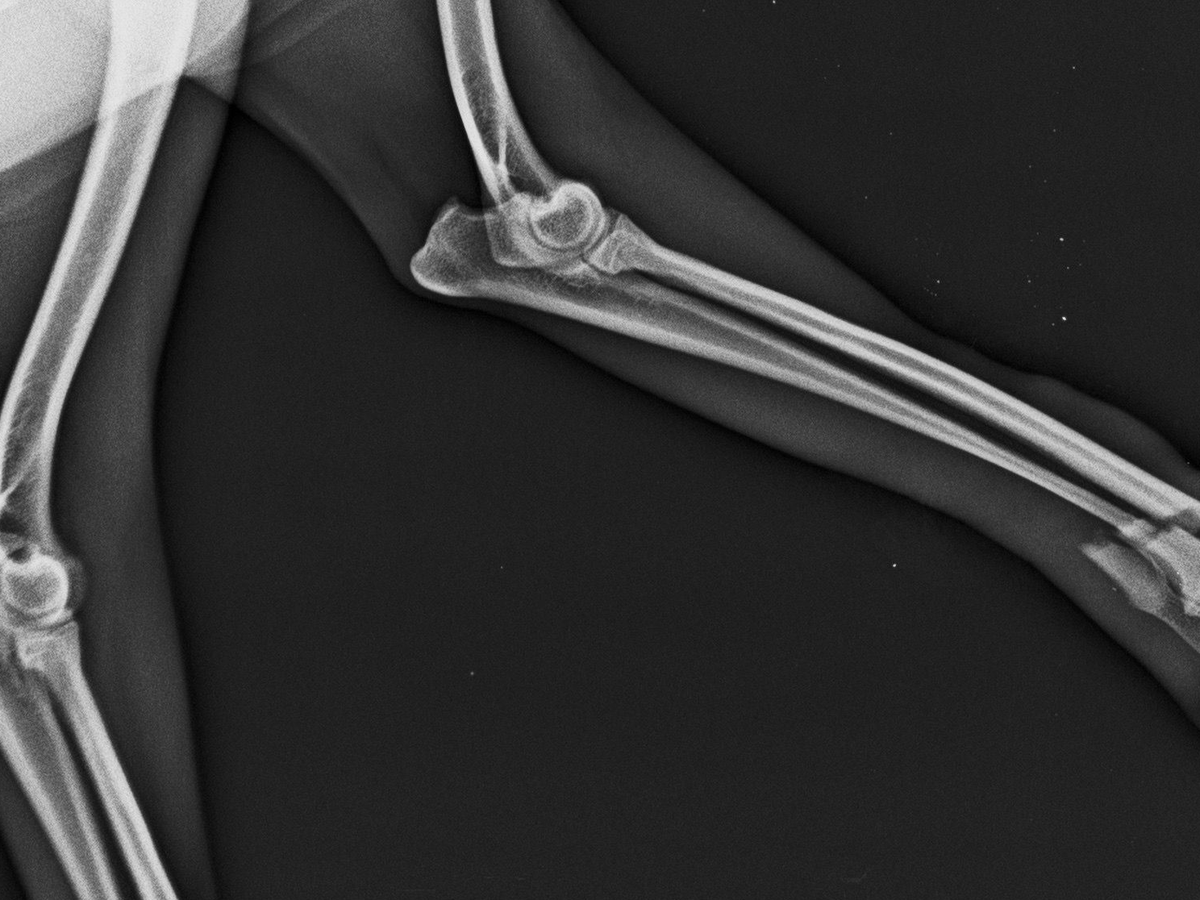

La hemos llevado al veterinario y nos han dado un diagnóstico un tanto complicado el cual es : Fractura Transversa cerrada con desplazamiento de radio y cubito.